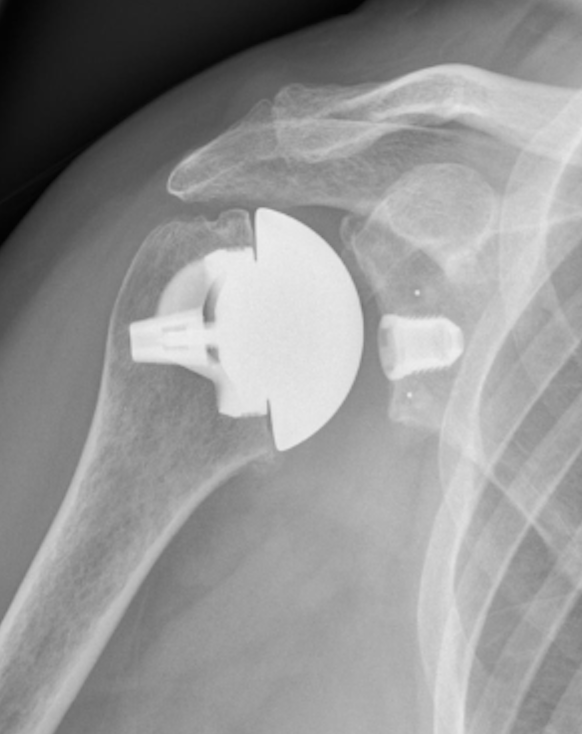

• Arthroskopische Rotatorenmanschettenrekonstruktion – minimalinvasive Nahttechniken für akute und chronische Läsionen • Schulterinstabilität & Bankart-Behandlung – indikationsgerechte Stabilisierung mit modernen arthroskopischen Verfahren • AC-Gelenksyndrom & distales Schlüsselbein – operative Rekonstruktion und stabile Wiederherstellung der Gelenkfunktion • Ellenbogenchirurgie – operative Versorgung von Sehnenverletzungen, Instabilitäten und komplexen Läsionen • Schulterendoprothetik (anatomisch & invers) – endoprothetische Versorgung bei Arthrose, Frakturfolgezuständen und Defektarthropathie